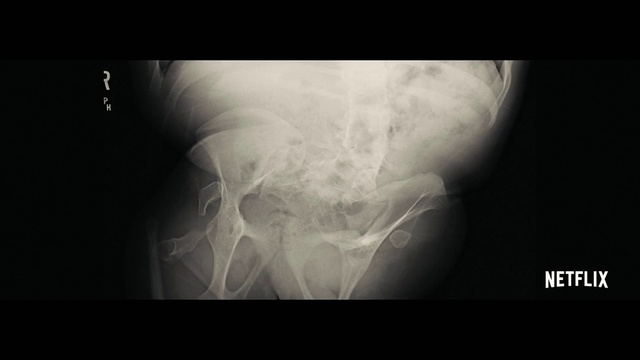

Best Video References: Fracture

Featured videos selected by a smart neural network algorithm